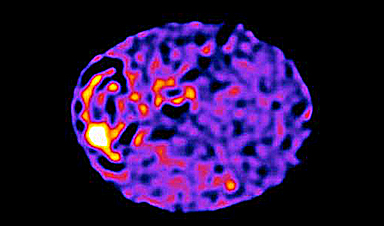

Cells in the body are wired like computer chips to direct signals that instruct how they function, research suggests (Nature Communications, “The cell-wide web coordinates cellular processes by directing site-specific Ca2+ flux across cytoplasmic nanocourses”).

Researchers at the University of Edinburgh found information is carried across a web of guide wires that transmit signals across tiny, nanoscale distances.

It is the movement of charged molecules across these tiny distances that transmit information, just as in a computer microprocessor, the researchers say.

These localised signals are responsible for orchestrating the cell’s activities, such as instructing muscle cells to relax or contract.